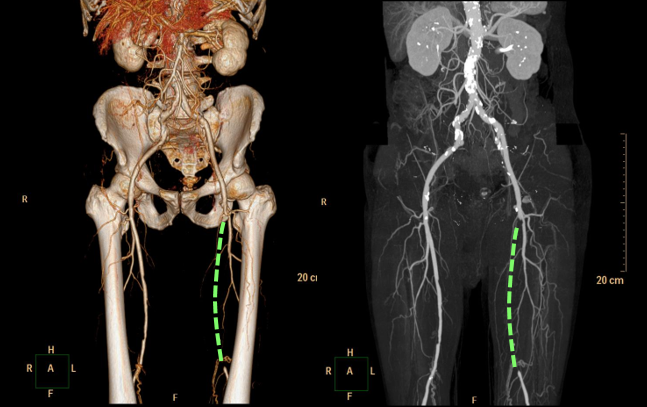

CTやMRIによる精密検査

より詳細な情報が必要な場合や、カテーテル治療、手術を検討する際には、血管造影CT検査が行われます。造影剤を注射してCT撮影を行うことで血管の立体的な画像を取得でき、どの血管が、どの程度、どのくらいの長さにわたって狭くなったり詰まったりしているのかを正確に把握することができます。